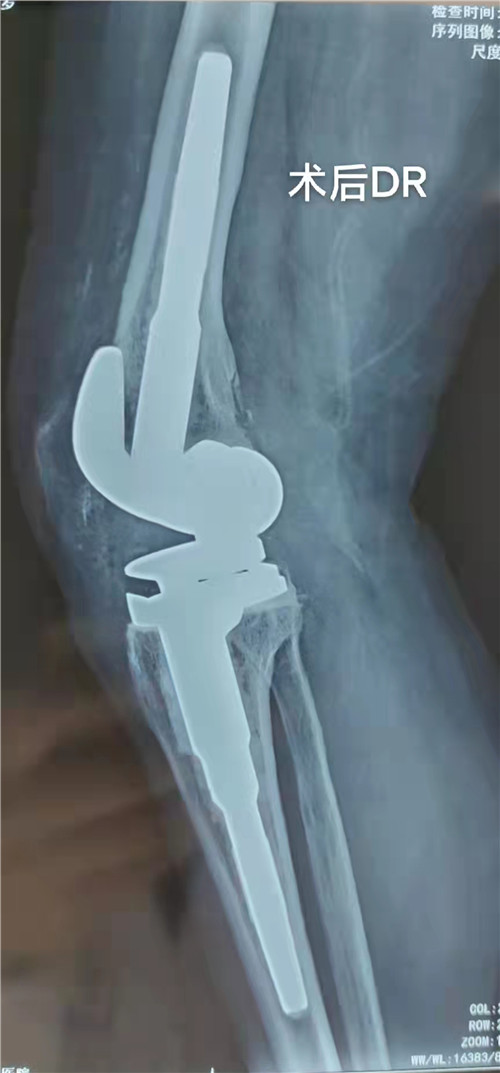

经骨一科主任邵建敏和副主任徐军志反复查阅相关资料及科室病例讨论后,与患者及家属沟通并征得同意后,建议行右膝关节铰链式人工膝关节置换手术。完善检查排除手术禁忌后于12月18日在腰硬联合麻醉下为患者行右膝关节铰链式人工膝关节置换手术,术中情况复杂:患者膝关节融合,关节间隙消失,屈曲功能丧失,只能先经验性截骨后使膝关节屈曲得到恢复,后发现膝关节截骨器械无法适配,且患者既往曾行软组织松解手术,术中腓总神经极易损伤。凭借丰富的手术经验,主刀医师在没有借助测量器械的情况下反复修整截骨最后顺利置入假体,术中膝关节活动良好。术后患者踝关节活动正常,术后3天拔管下床活动,右膝屈伸0°-30°,术后经管医师每周随诊,追踪患者功能恢复情况,指导患者功能锻炼,现患者右下肢功能恢复良好,生活质量明显提高,缓慢行走时基本与常人无异。